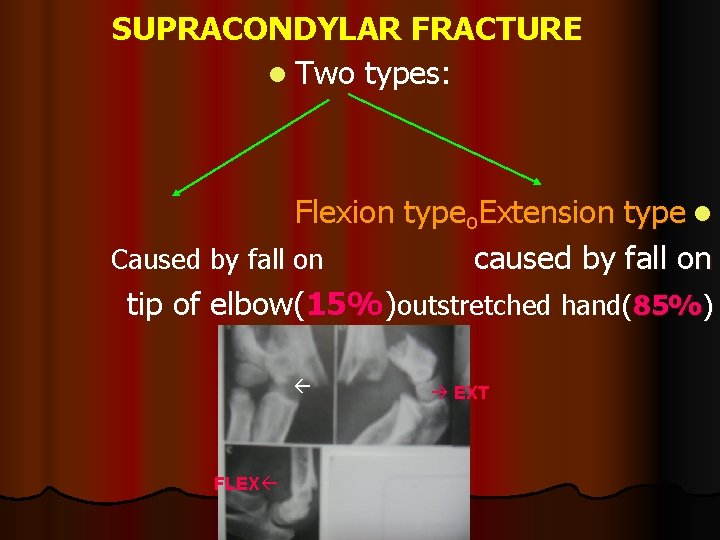

SUPRACONDYLAR FRACTURE l Two types: Flexion typeₒExtension type l Caused by fall on caused by fall on tip of elbow(15%)outstretched hand(85%) FLEX EXT